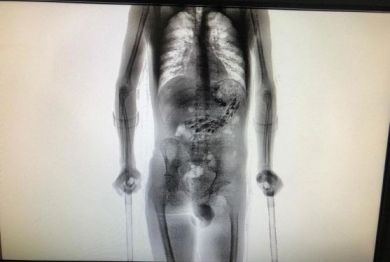

Fugiu do Hospital Regional de São José, na Grande Florianópolis, um detento que estava hospitalizado para expelir invólucros contendo objetos estranhos no estômago. O homem, identificado como Edson Jhonas Pagini de Oliveira, 24 anos, foi internado após tentar entrar na Colônia Penal Agrícola de Palhoça com os materiais, na tarde de terça-feira (15), em retorno após saída temporária. No momento do flagra, Edson estava com outro detento, que tinha 10 celulares e mais 52 invólucros no aparelho digestivo. Os dois foram submetidos a scanner corporal no Complexo Penitenciario de São Pedro de Alcântara.

O flagra do colega de Edson chamou a atenção até mesmo dos agentes mais antigos do sistema prisional. No estômago do detento foram encontrados dez celulares e 52 invólucros contendo cabo USB, isqueiro, chips telefônicos, drogas e outros objetos.